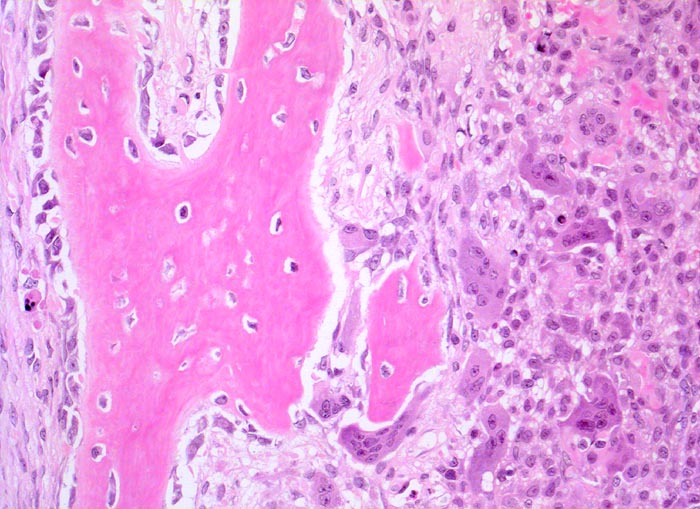

aneurysmatische Knochenzyste (AKZ)

Neugebildeter Faserknochen mit Osteoblasttapete. Daneben dichtliegende mononukleäre Zellen und mehrkernige Riesenzellen. Streifenförmige besenreiserartige Matrixbildung.

Lokalisierte Schmerzen und Schwellung in der proximalen Fibula. Im Röntgenbild ist eine Osteolyse erkennbar, die die betroffene Fibula auftreibt. Die Cortikalis über der Osteolyse ist hauchdünn.

Histologie

200